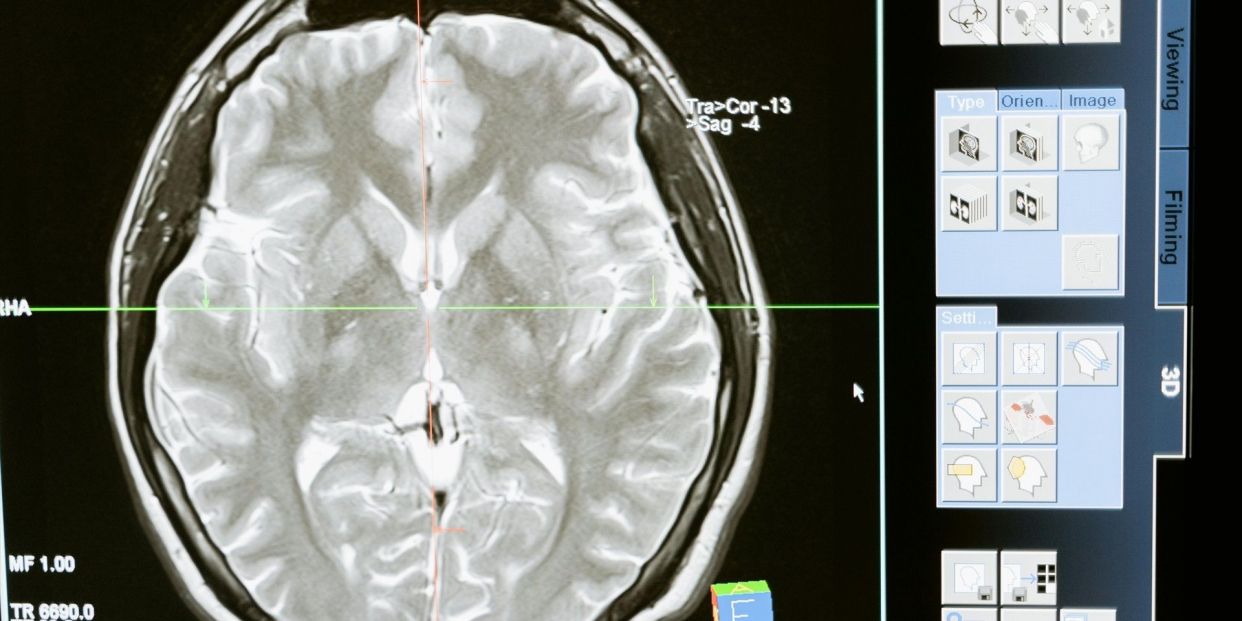

El ictus isquémico es un accidente cerebrovascular consistente en un coágulo sanguíneo que evita que la sangre fluya hacia el cerebro provocando la muerte de las células de este órgano en cuestión de minutos.